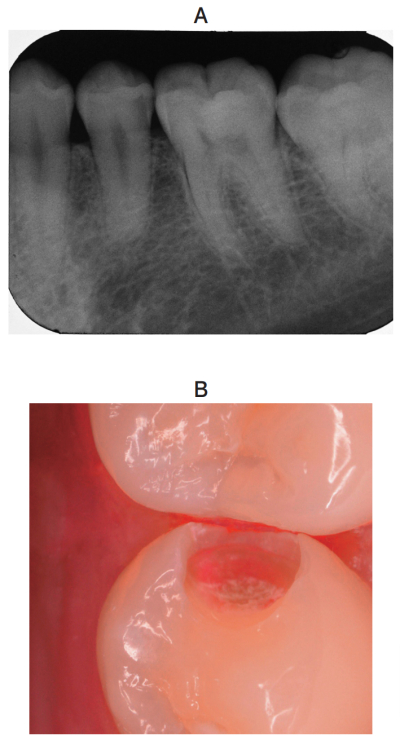

25 歳の男性。下顎左側第二小臼歯の一過性の冷水痛を主訴として来院した。歯髄電気診で生活反応を示した。コンポジットレジン修復を行うこととした。初診時のエックス線写真と窩洞形成後の口腔内写真を別に示す。

窩洞の C ファクターはどれか。1つ選べ。

修復に際し適切なのはどれか。2つ選べ。